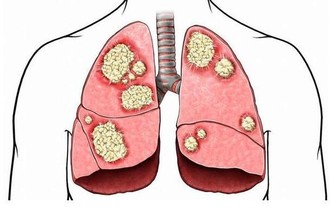

腎臟是我們的身體中最重要的器官,它們負責預防許多疾病,執行身體的整體機能。

其中一個最重要的功能是清除血液中的廢物和毒素。

許多因素會使我們的腎臟衰弱,造成腎臟疾病,甚至引起嚴重的後果。